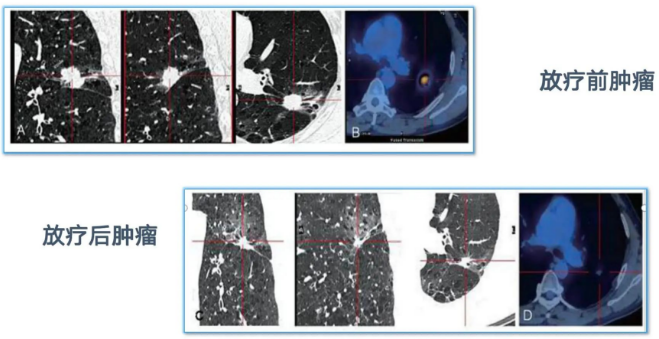

团队年肺癌放疗量在400例以上,常规开展3D-RCT、IMRT、VMAT等调强放疗技术,肺癌立体定向放射治疗(SBRT)在粤西首先开展,海马保护、毛囊保护的肺癌脑转移脑部放射治疗与中国科学院大学附属肿瘤医院合作完成,为国内较早开展。晚期肺癌年治疗4000人次以上,紧跟国内外指南规范地开展肺癌新辅助免疫联合化疗、辅助化疗和靶向治疗、姑息性靶向治疗、免疫治疗、抗血管生成治疗、肺癌脑转移放疗和肺癌全程管理等综合性治疗。参加多项国际、全国多中心肺癌临床研究,为广大患者提供使用新药的机会。

肺部病灶SBRT新技术粤西首先开展